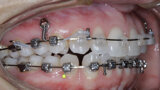

New Age orthodontics and orthopaedics with temporary anchorage devices